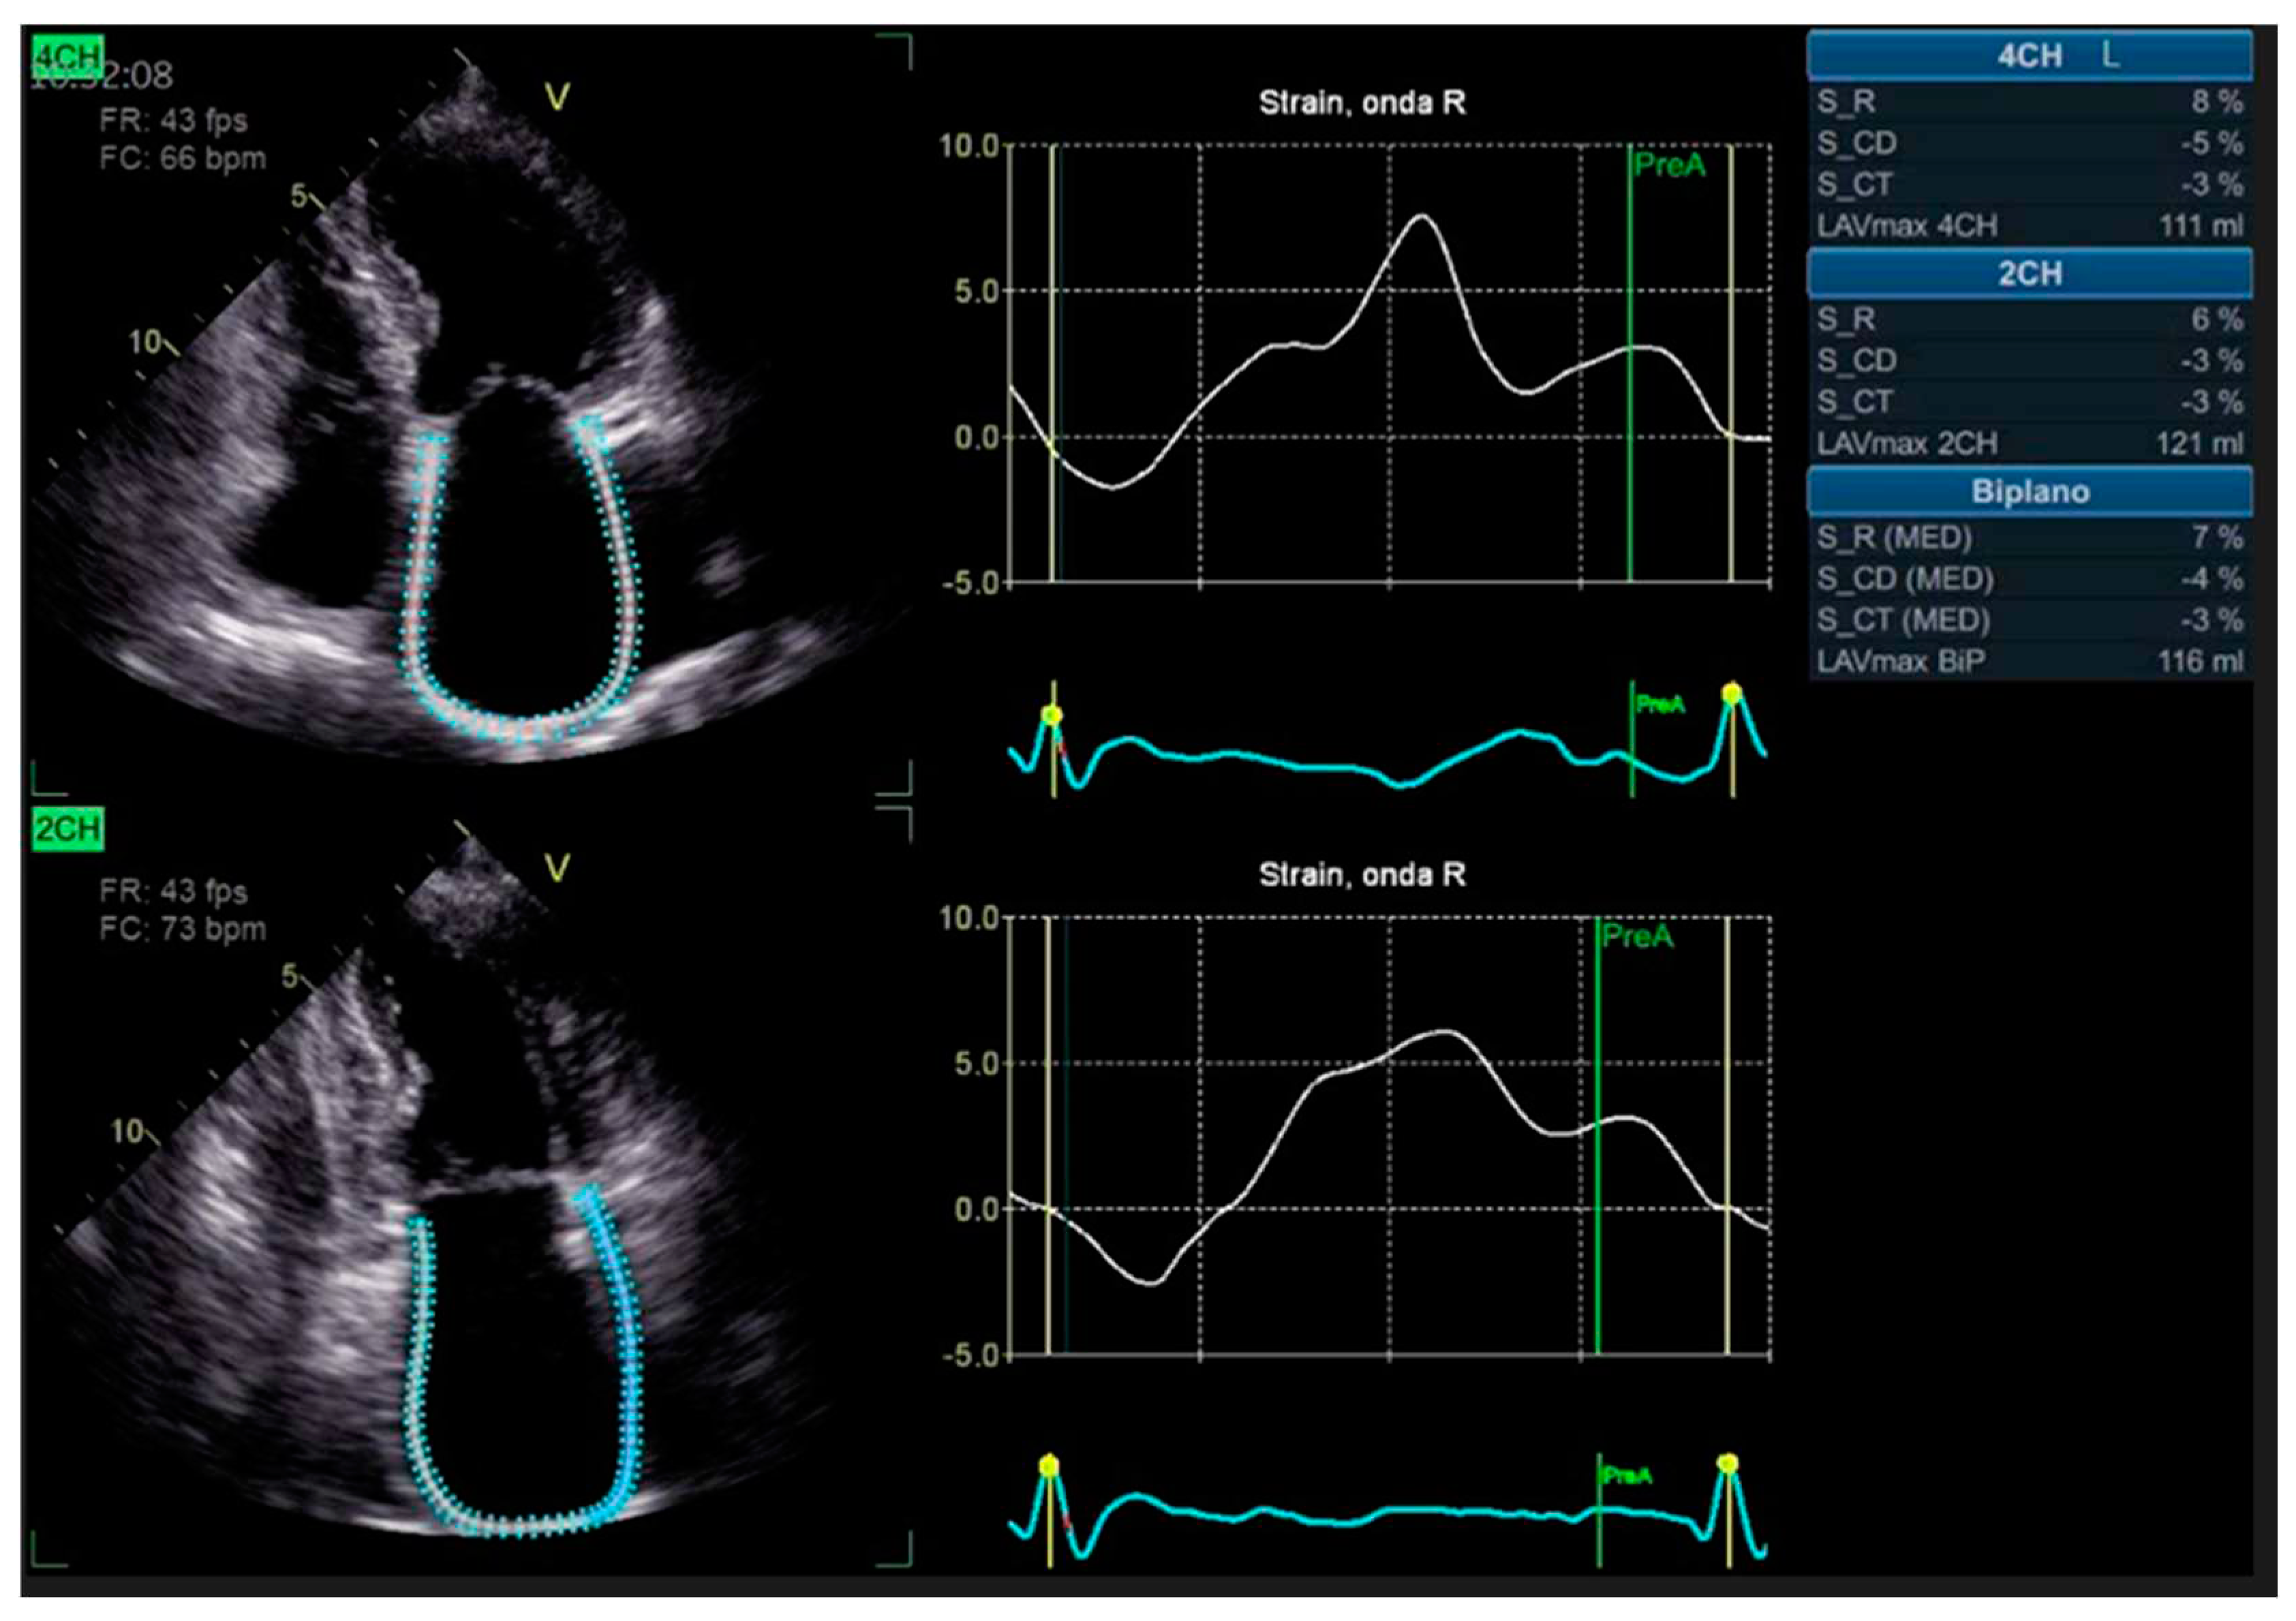

The integration of intravascular ultrasound (IVUS) with coronary angiography reveals approximately 19% more cases of CAV, making it the most sensitive test available for monitoring CAV progression in the clinical setting [42]. However, CCTA has been proposed as an alternative to IVUS for routine follow-up of HT patients due to its superior spatial resolution [43]. In a recent meta-analysis, the sensitivity, specificity, positive predictive value, and negative predictive value of CT for detecting CAV were reported as 97%, 81%, 78%, and 97%, respectively [44]. Nevertheless, there is currently no standard method available for the assessment of CAV on coronary CTA images, and distinguishing CAV from atherosclerotic lesions can be challenging [Figure 2 and Figure 3].

Figure 2. Cardiac computed tomography images showing cardiac allograft vasculopathy grade III according to the International Society for Heart and Lung Classification. Right coronary artery reconstruction with a calcific coronary plaque at the second tract assessed by cardiac computed tomography angiography (right panel) and his orthogonal views (left panel).